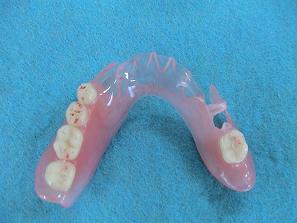

5歯欠損

2. 作製したバネなし入れ歯

(バルプラスト)です